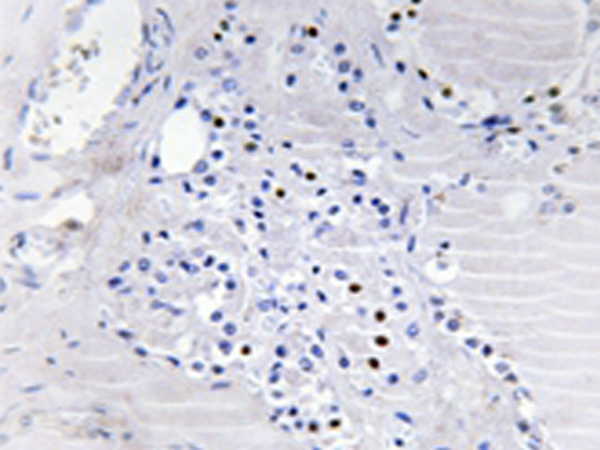

IHC positive control: |

Human thyroi glan tissue |

IHC Recommend dilution: |

50-100 |